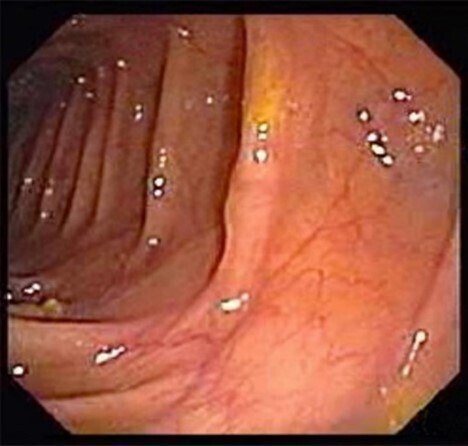

L’endoscopiste vous adresse les images clés suivantes et vous indique que l’examen a permis d’explorer l’ensemble du côlon ainsi que la valvule iléo-caecale.

Question 6 - Vous estimez que (une ou plusieurs réponses exactes) :

Seule une masse est visible.

La muqueuse est globalement saine.

La muqueuse colique est globalement saine mais on distingue une masse anormale sigmoïdienne.